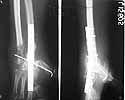

I would like to give a 5 month follow up of this case.

At about two months post initial surgery, fingers were mobilised and a formal wrist arthrodesis was done along with resection of distal ulna to give some rotational movement of forearm. He was given an eight week immobilisation of wrist and then further mobilisation of fingers were given. Some of present functional pictures are attached. In the meantime the original team which treated this patient has moved out of the centre to different parts of the globe and he is continuing follow up with the available team member in this country. May be patient's persistence has given the result thus far.

Would welcome your valuable comments.